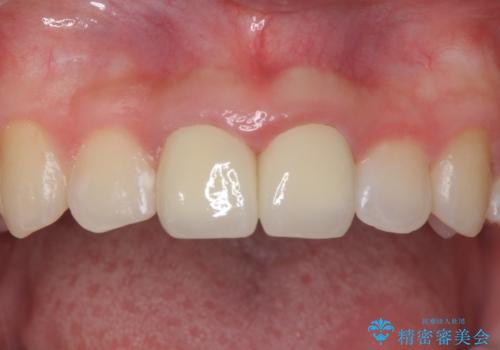

また、プラスチックでつぎはぎになっていたため、虫歯を取りしっかりとしたクラウン(被せもの)としました。

前歯の変色及び、ガタガタもしっかりなおり、満足していただきました。